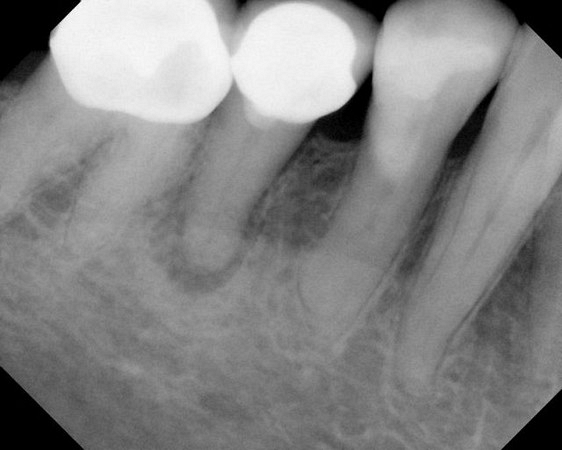

Here are examples of digital dental radiography